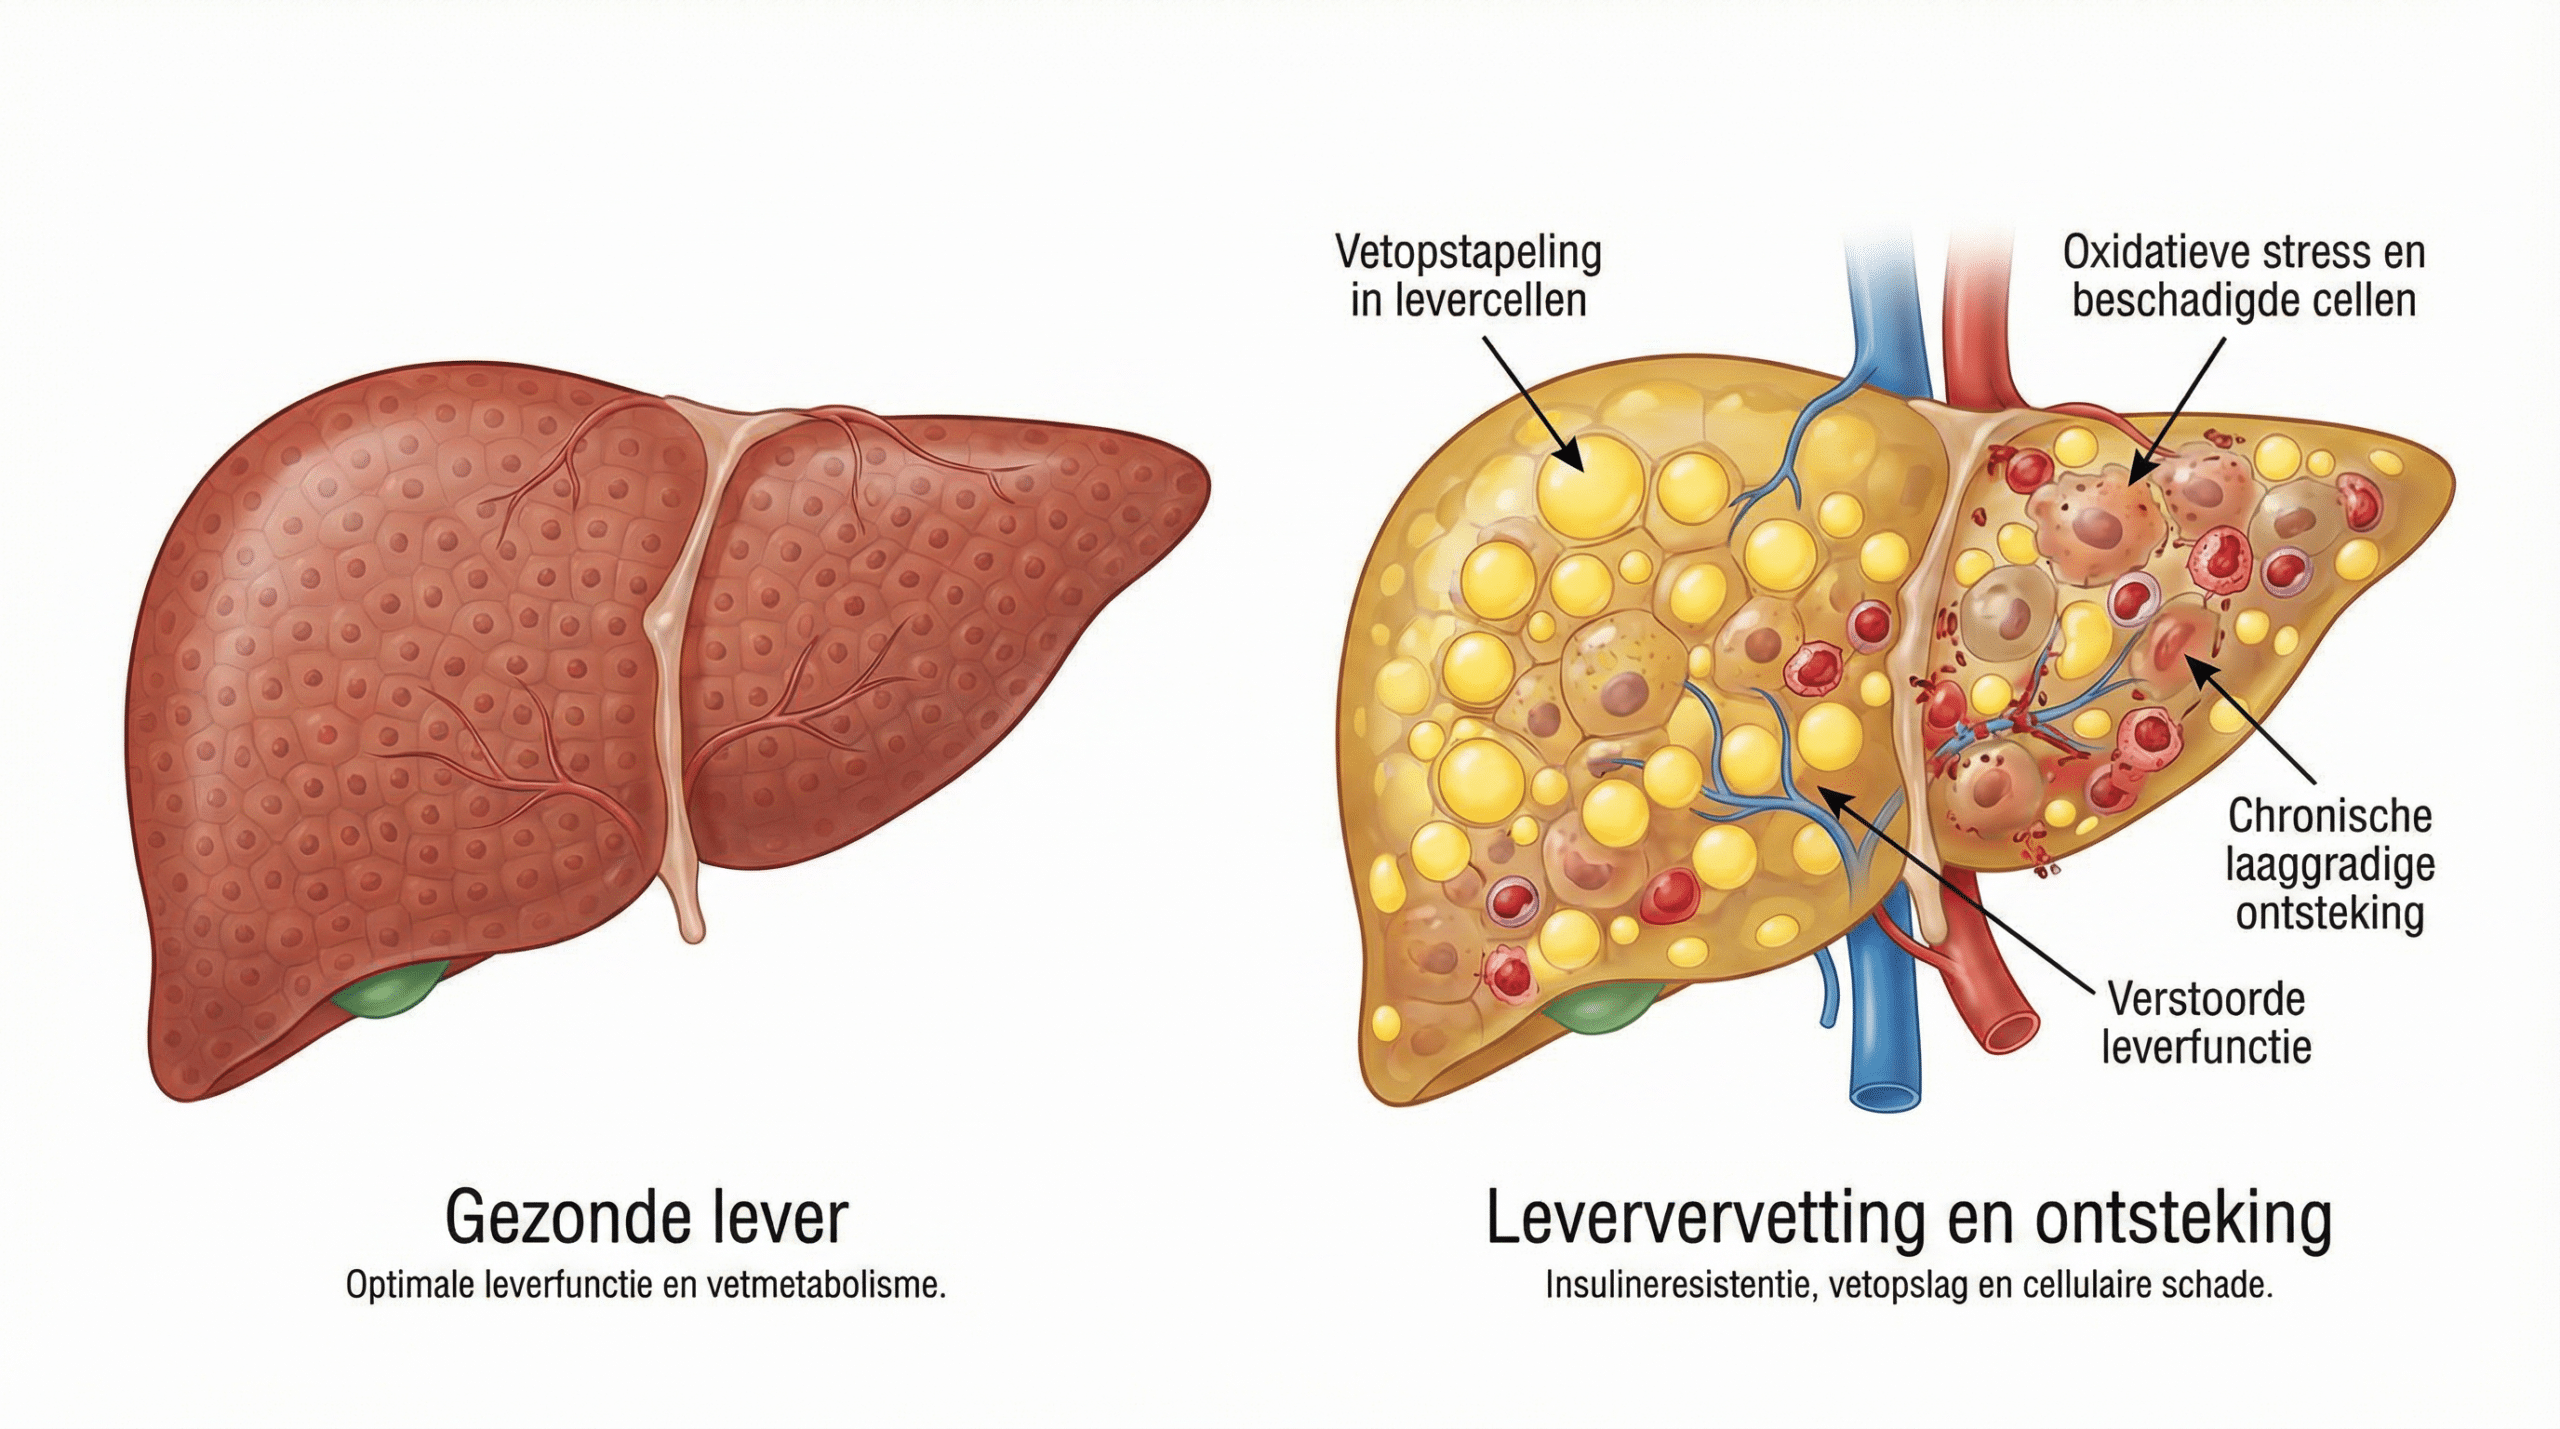

Om het verschil te begrijpen, moeten we eerst begrijpen hoe de lever vet verwerkt en wat er misgaat bij leververvetting.

De lever verwerkt normaal gesproken vetten efficiënt — maar wanneer er meer vet binnenkomt dan de lever kan verwerken, begint het overtollige vet zich op te stapelen in de levercellen zelf.

Een gezonde lever met een goed functionerend metabolisme verwerkt vetten soepel en houdt de leverenzymen binnen normale waarden.

Kijk nu naar een aangetaste lever.

Door vetopstapeling raken levercellen beschadigd — de kleine vetdruppeltjes in de cellen verstoren de normale leverfunctie, veroorzaken oxidatieve stress en activeren ontstekingsreacties die de schade verder uitbreiden.

Het is als een overbelaste fabriek die haar eigen afval begint op te slaan.

Op een gegeven moment raakt het systeem verstopt — en begint de schade zich uit te breiden naar het omliggende leverweefsel.